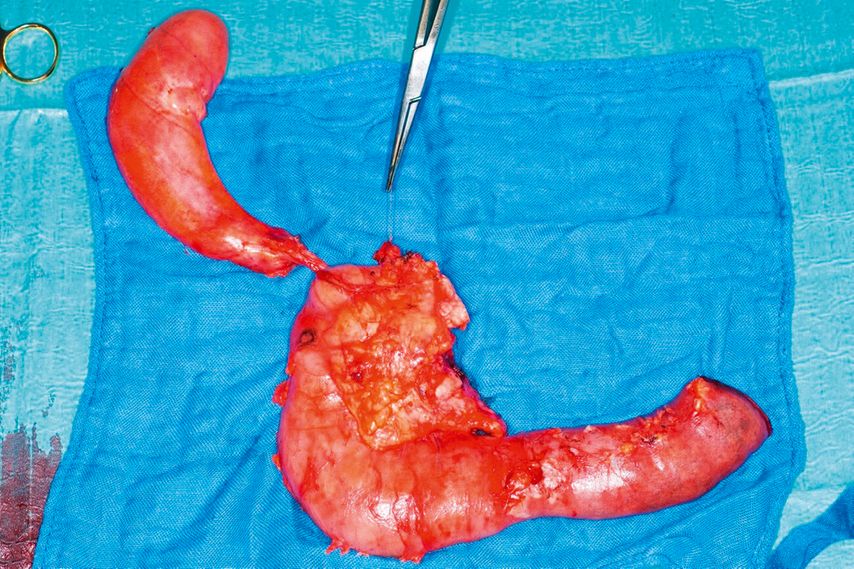

Bei periampulären Tumoren oder Tumoren des Pankreaskopfs wird die Duodenopankreatektomie durchgeführt. Dabei werden Gallenblase, distaler Gallengang, Duodenum, Pankreaskopf und Processus uncinatus des Pankreas reseziert und es wird eine standardisierte Lymphadenektomie durchgeführt (Abb. 1).

Abb. 1: Bei periampulären Tumoren oder Tumoren des Pankreaskopfs erfolgt eine Duodenopankreatektomie